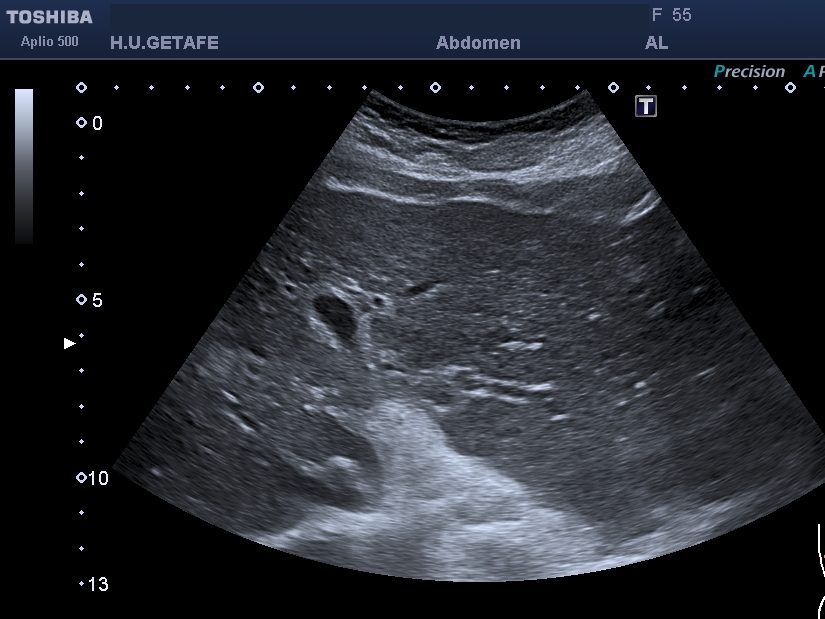

La exploración comienza colocando el transductor en la posición adecuada para visualizar el tendón del subescapular, similar a la técnica utilizada en sedestación. Luego, se realiza un movimiento pasivo del brazo del paciente, quien debe mantenerlo en flexión y abducción de aproximadamente 90 grados. El operador manipula el brazo para encontrar la mejor visualización del labrum anterior, situado en una posición más profunda.

Además del labrum anterior, esta técnica también permite una evaluación detallada de la articulación gleno humeral y la cápsula articular anterior. Estas observaciones son esenciales para un diagnóstico completo, ofreciendo una comprensión integral de la articulación del hombro.